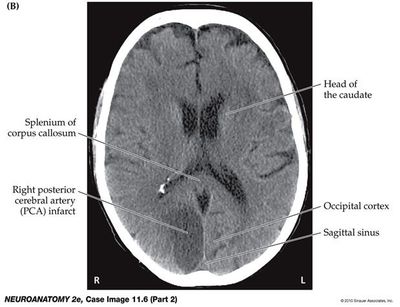

R PCA infarct of entire R PVC would cause which visual deficit?